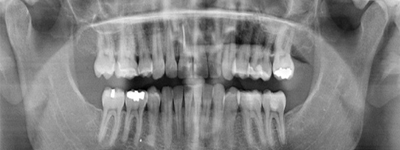

El escáner dental 3D captura imágenes detalladas de la boca, permitiendo una representación tridimensional de los dientes y las estructuras circundantes. Estas imágenes precisas se utilizan para el diseño y fabricación de piezas dentales

La fresadora dental, en combinación con el escáner más el software de diseño digital de prótesis dentales, son nuestras herramientas más exactas y detalladas para realizar prótesis dentales de máxima precisión y estética.